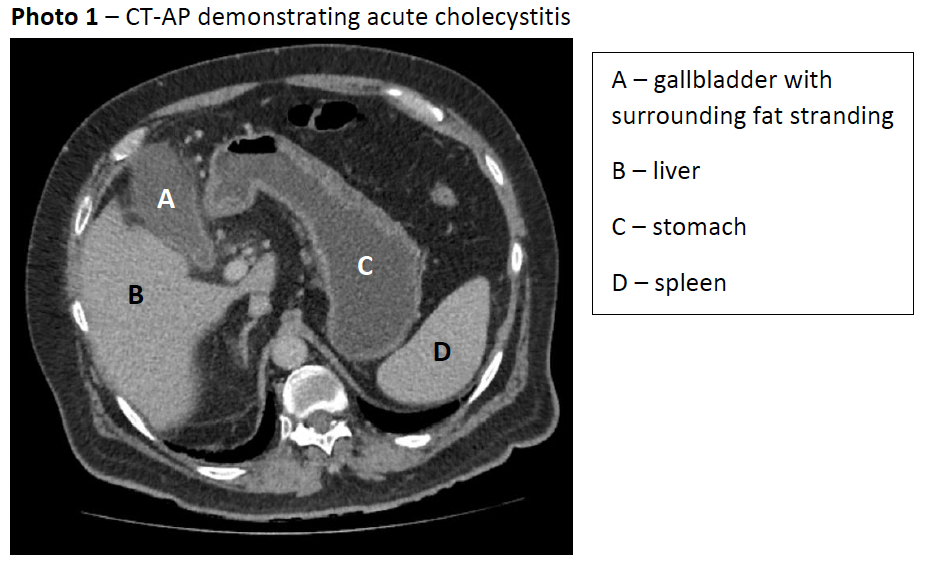

The patient’s bloods showed a lactate of 2.0mmol/L, white cell count of 14.0x109/L, normal electrolytes/urea/creatinine, slightly elevated total bilirubin of 24μmol/L but otherwise normal liver function tests. A computed tomography of the abdomen and pelvis (CT-AP) was performed which demonstrated pericholecystic free fluid and a mildly thickened gallbladder wall and normal common bile duct diameter (3mm), in keeping with acute cholecystitis in the absence of radio-opaque gallstones (photo 1). An abdominal ultrasound (photo 2) the next day confirmed CT findings with no gallstones seen, indicating AAC.